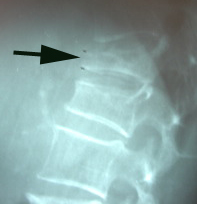

Fortunately it is a rare occurrence, but pregnancy- and lactation-associated osteoporosis occurs. Manahawkin Chiropractic Center closely watches our Manahawkin pregnant patients or women in postpartum period to see if they develop incessant back pain, especially if they have risk factors or secondary causes of osteoporosis. What comes of pregnancy-associated-osteoporosis? Vertebral fractures. (1)

A new case report offers hope for conservative care of vertebral fractures. A woman with seven vertebral compression fractures was treated conservatively with strontium ranelate and supplementation of calcium and cholecalciferol. (2) 7 fractures! Wow. This treatment combination quickly restored the bone mineral density value in this case. Imagine if you have just one fracture!

Vertebral fractures as a result of osteoporosis - pregnancy-associated or lactation-related or genetically-linked - are not to be taken lightly. Manahawkin Chiropractic Center is the chiropractic healthcare provider to trust to find and/or manage their healing. So if you are pregnant and experience back pain, contact Manahawkin Chiropractic Center. You will be examined carefully and treated gently. Our other Manahawkin pregnant ladies so appreciate the gentle stretching we can achieve with Cox Technic, even in the later months of pregnancy. If you are pregnant and have a family history of osteoporosis, contact Manahawkin Chiropractic Center for some advice to ward off its effects. Exercise, nutrition, and chiropractic treatment may be part of the treatment plan.